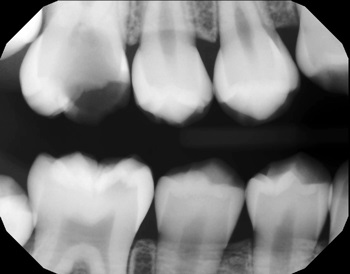

FIGS. 7 AND 8: Initial bitewings.

permanent first molar extraction